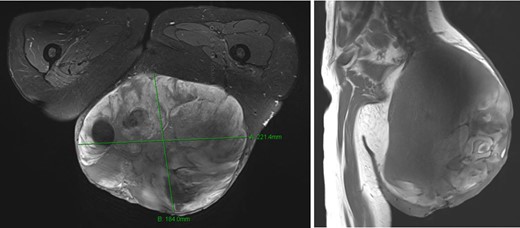

A woman 36 years of age presented with a painless, slowly growing mass of the left buttock (Fig. 1). Magnetic resonance showed an inhomogeneous tumor of 10 × 8.5 × 6 cm3 in size suspicious for myxoid sarcoma (Fig. 2). Biopsy was recommended. However, the patient refused and was lost for follow-up. Three an a half years later, the anemic patient was referred again, now with a giant 22 × 19 × 24 cm3 measuring, foul, ulcerating and bleeding tumor (Fig. 3), partly infiltrating the gluteus maximus muscle (Fig 4). Myxoid sarcoma was confirmed by three deep punch biopsies in local anesthesia followed by swift surgical resection.

Magnetic resonance imaging showed a very large tumor of the left gluteal region, further infiltrating the left gluteus muscle and now with infiltration of the skin.